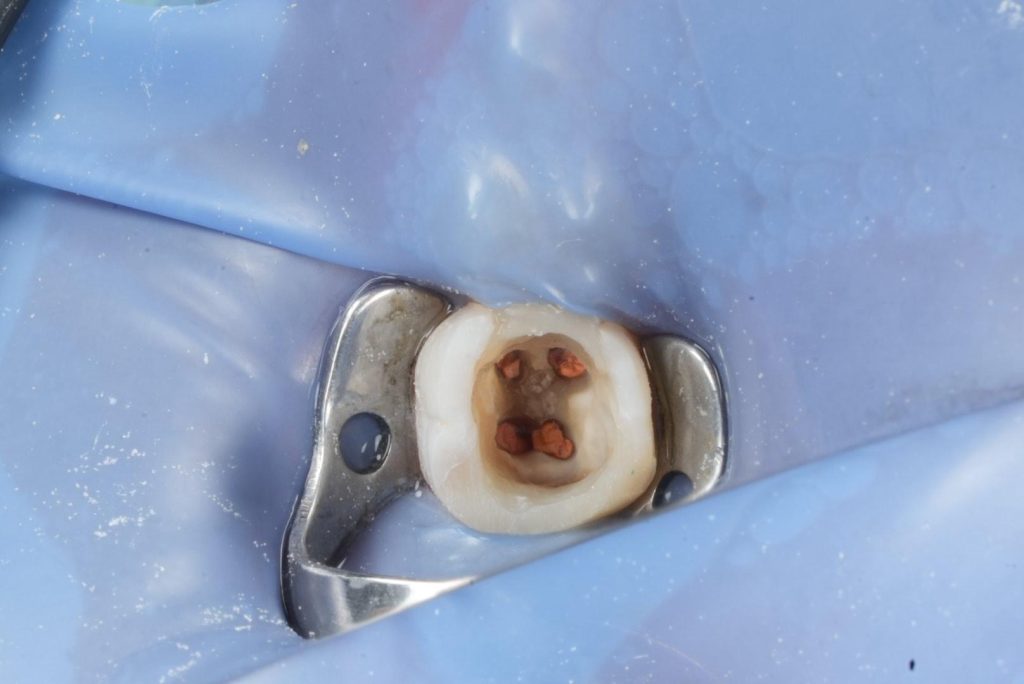

Endodontic Retreatment

- Rubber dam isolation applied throughout the procedure.

- Existing composite removed; defective margins corrected.

- Previous root filling material removed using rotary retreatment files and solvents.

- Working length established using electronic apex locator.

- Full irrigation protocol activated using:

- 5.25% NaOCl (heated)

- 17% EDTA

- Ultrasonic activation

- Apical patency regained and canal shaping completed using reciprocating NiTi files.

- Canals obturated using warm vertical compaction and bioceramic sealer to optimise apical seal.

- Immediate coronal seal placed post-obturation to prevent reinfection.

Deep Margin Elevation (DME)

- Distal subgingival margin elevated using flowable resin (GC EverX Flow / Equivalent).

- Garrison sectional matrix used to ensure tight proximal contact and emergence profile.

- Adhesive protocol respected to optimise bond.

Definitive Restoration

- Core build-up completed using dual-cure composite core material.